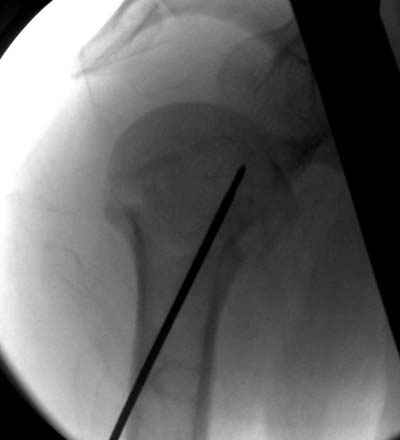

Здравствуй Женя. Во первых спицы, вводимые в головку плеча ретроградно, никогда не имели V-образную форму, если говорить о методике моей операции ЦИТО. Чтобы легче было запомнить Y-образную форму, вспомни крепление новогодних елочных шаров - очень демонстративно. Кроме того если ты внимательно посмотришь, то увидишь, что вся конструкция имеет некоторую кривизну по плокскости, величину, которой ты можешь задать сам. Сначала мы проводим проксимальный пучок, а в момент пересечения линии перелома мы

ротируем спицу таким образом, чтобы дистальный изгиб прямо противодействовал смещающим силам - поврот за ушко под контролем ЭОПа. Дистальный пучок стараемся провести так, чтобы его бранши расклинились и прошли по обе стороны предыдущего пучка, что создает дополнительное напряжение на

протяжении контакта. Для оценки правильности проведения спиц очень важно, чтобы ЭОП стоял строго перпендикулярно плоскости сустава, в противном случае - в рентгене есть эффект отбрасывания тени - прохождение косого луча дает удлиненное изображение спиыц и создается впечатление, что спица стоит уже в субхондральном слое. На первых операциях у нас было довольно частое несовпадение длины контрольной спицы и мы провизорно добавляли от 0,5 до 1,0 см уже на фиксирующем пучке. Входные отверстия лучше располагать по наружной и передней поверхности плеча на расстоянии не менее 2-х диаметров головки.

Такой выбор входных отверстий обусловлен прямой возможностью попадания в малый и большой бугорки за счет изгиба спиц по длине и отражения из от внутреннего кортикала проксимальнее точки введения. Поскольку анатомически бугорки не составляют артикулирующую поверхность, то некоторое выстояние спиц только усилит стабильность. Входное отверстие мы используем 6 мм в диаметре, для эффективного раскрытия петли-пружины. Спицы перед проведением

проверяем на достаточную эластичность и упругоустойчивость, мягкие спицы отбраковываем. В данном примере создалось впечатление, что одна бранша V-спицы скользнула по картикалу снаружи? Все это безболезненно можно переделать, расширив теже отверстия, изогнув спицы, повернув их в разные стороны и добавив еще пучки Y-ОБРАЗНЫХ, а не V-образных (эти пучки выталкивает, особенно если они прямые - пружина работает в обе стороны).

Сегодня взял больного повторно в операционную, не скажу, что повторная репозиция через неделю после первой попытки, была простая.

После удаления спиц попытался манипулировать отломками, но безуспешно, поэтому пришлось пользоваться периостальным элеватором, чтобы устранить смещение отломков и перепровести спицы. Проверил и перепроверил стабильность фиксации под ЭОПом, завтра Рг- будет готов, вот и поглядим....

Я и сам доволен результатом. В предпоследнем письме я кратко описал ход операции - закрыто репонировать не удалось( 2 недели с момента травмы и 1 неделя после неудачной репозиции) после удаления пучков спиц, пришлось сделать - 2см разрез на уровне перелома и с помощью периостального элеватора (золотое правило механики) *одеть* головку на дистальный отломок.

Спицы проводил через старые отверстия, вращая пучок импактором- направителем при его введении в головку.